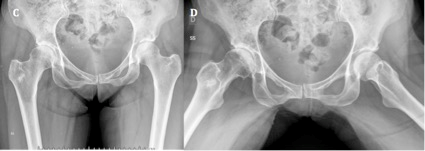

Figura 4: Siete meses postoperatorios. A) Se observa aumento de esclerosis subcondral y disminución de la luz articular. B) Perfil de ambas caderas donde se visualiza el estrechamiento articular en polo superior.